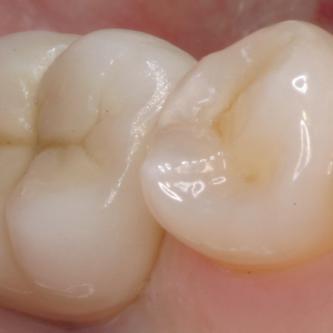

Exemple 2: Un implant remplaçant la racine d'une molaire inférieure gauche.

Exemple 2: La couronne en céramique scellée sur cet implant.